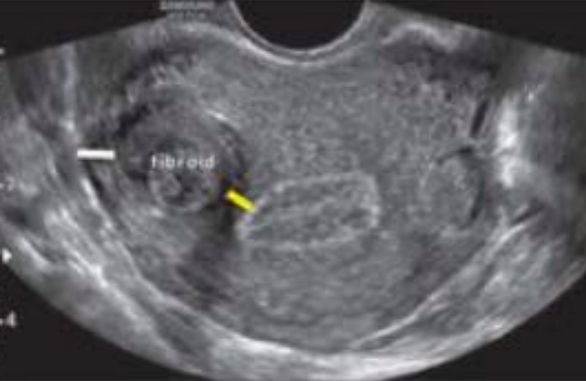

What type of fibroid is depicted in this image?

A. Intramural

B. Submucosal

C. Subserosal

D. Pedunculated

Subserosal

Name the type of fibroid and its location

Pedunculated

Anterior

Intramural

Posterior

Submucosal